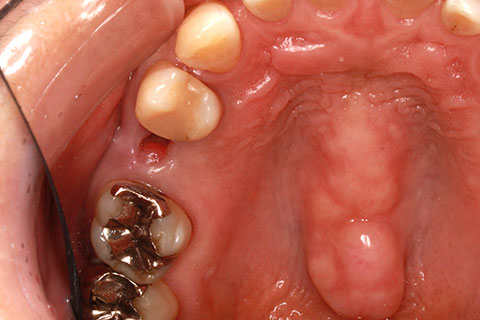

ジルコニアブリッジの症例2

- 年齢・性別

- 40歳男性

- 治療期間

- 1ヶ月

- 抜歯

- 右上5番欠損

- 治療費

- 16.5万円

- 備考

- 歯質の削除量を最小限に抑えるブリッジ治療

- 治療内容

- 欠損部位の隣接歯を削合後、セメント合着

- 施術の副作用(リスク)

- 知覚過敏、歯髄炎、荷重負担